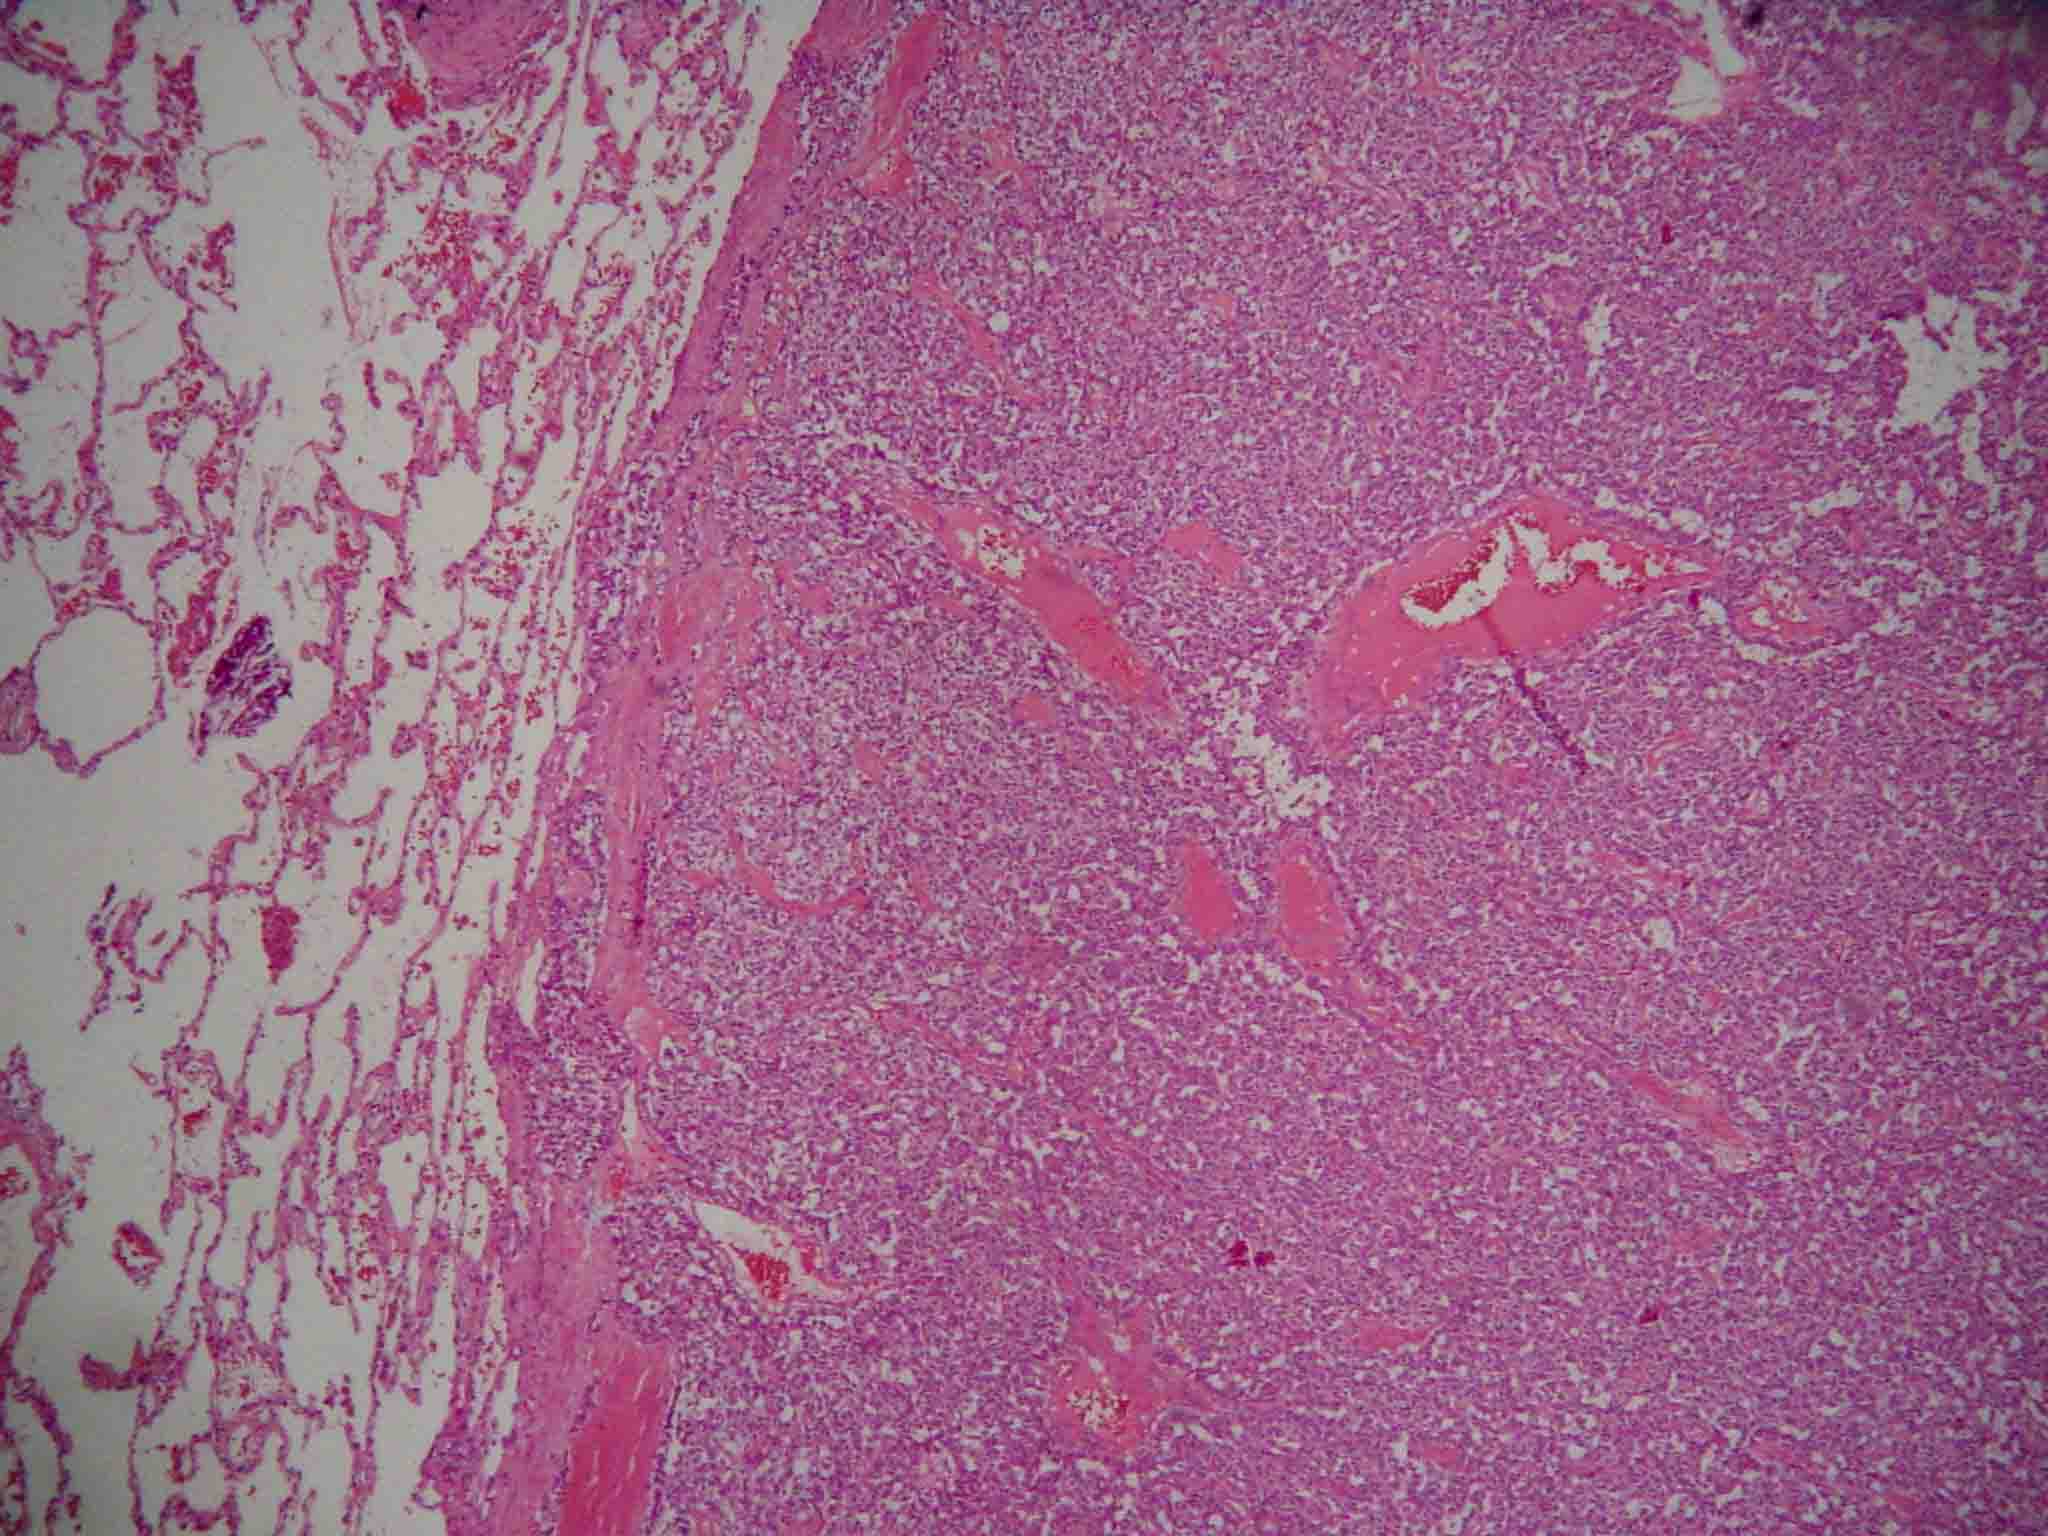

Carcinoid tumor is a serotonin-producing malignant tumor belonging to a class of neoplasms known as the neuroendocrine tumors. Carcinoid tumors of the lung are much less common and represent 1% to 2% of all lung cancers. The current classification of lung tumors recognizes bronchial typical carcinoid as low-grade neuroendocrine tumors. Symptoms are usually related to local compression and obstruction of the bronchial tree. Preoperative diagnosis is usually obtained without bronchoscopic biopsy. The authors report the case of a woman with typical carcinoid tumor in the left lower lobar bronchus, next to the secondary carina. It was treated with bronchoplastic resection, and associated to lymphadenectomy. The complete surgical resection remains the only therapy with curative intent in the majority of patients. Local relapse can be treated successfully with surgery, whereas distant metastases have a poor prognosis even after chemotherapy.Downloads

- he1.jpg (Português (Brasil))